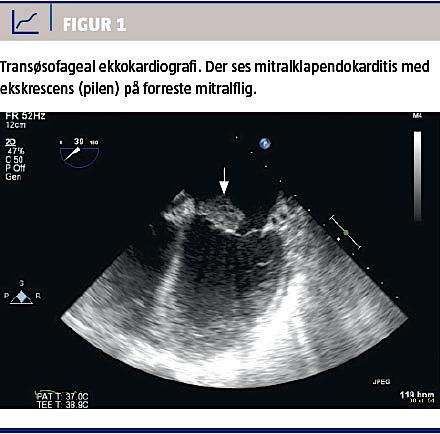

En antistofscreening inkl. screening for antinukleære antistoffer (ANA) og antifosfolipide antistoffer afslørede ingen abnormaliteter. Ved en transtorakal ekkokardiografi (TTE) sås der diskret mitralinsufficiens (MI). Bloddyrkningerne viste vækst af Staphylococcus aureus, som var følsom for cefuroxim, men pga. manglende bedring ordinerede man nye, tidsforskudte bloddyrkninger, der viste vækst af S. aureus, som var følsom for dicloxacillin. Patienten kunne ikke kooperere til transøsofageal ekkokardiografi (TEE), men en ny TTE viste mitralklapendokarditis og moderat MI. Hun blev derfor overflyttet til en højtspecialiseret enhed, hvor man udførte TEE (Figur 1) i generel anæstesi, og hun blev herefter mitralplastikopereret. Ved kontrol tre måneder senere afkræftedes mistanken om SLE, idet hun ikke længere havde udslæt, led- eller almensymptomer, og de biokemiske værdier var normaliseret.